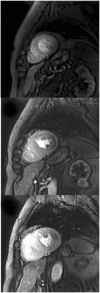

This document is an update to the 2013 publication of the Society for Cardiovascular Magnetic Resonance (SCMR) Board of Trustees Task Force on Standardized Protocols. Concurrent with this publication, 3 additional task forces will publish documents that should be referred to in conjunction with the present document. The first is a document on the Clinical Indications for CMR, an update of the 2004 document. The second task force will be updating the document on Reporting published by that SCMR Task Force in 2010. The 3rd task force will be updating the 2013 document on Post-Processing. All protocols relative to congenital heart disease are covered in a separate document.The section on general principles and techniques has been expanded as more of the techniques common to CMR have been standardized. A section on imaging in patients with devices has been added as this is increasingly seen in day-to-day clinical practice. The authors hope that this document continues to standardize and simplify the patient-based approach to clinical CMR. It will be updated at regular intervals as the field of CMR advances.